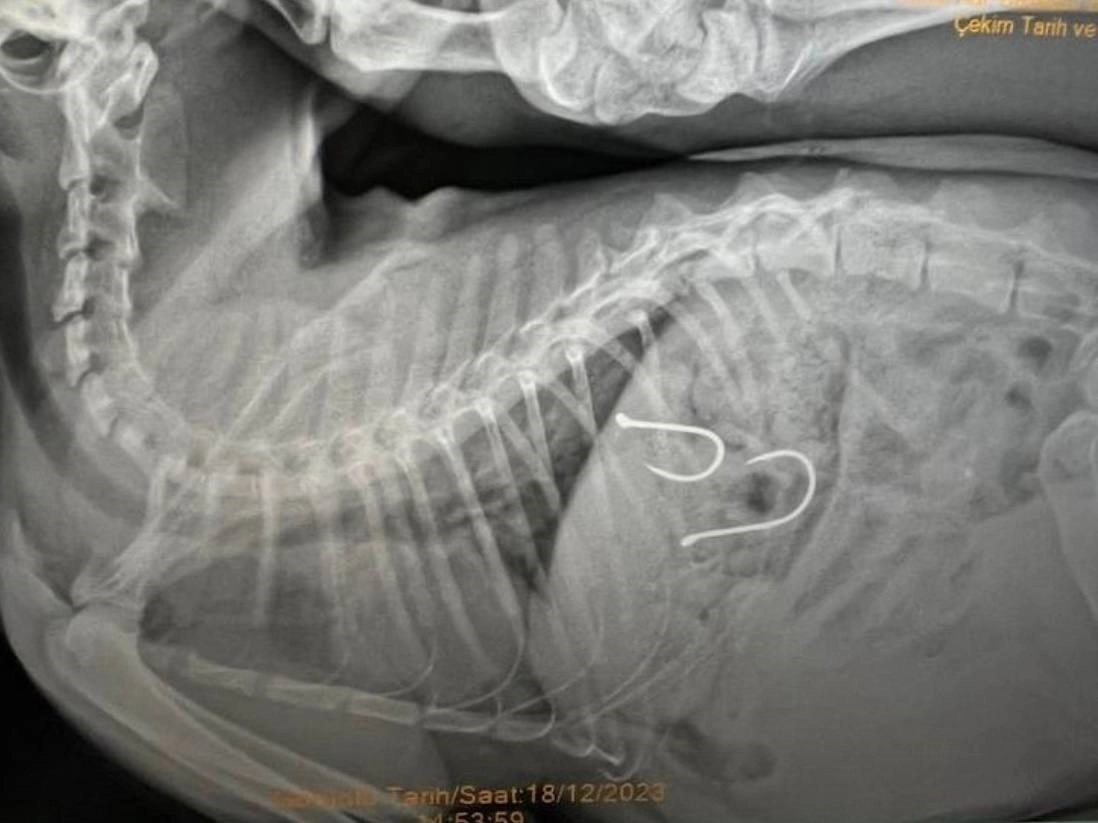

Sahil bandında dolaşan vatandaşlar, bir kedinin ağzından olta misinası sarktığını fark edince durumu Balıkesir Büyükşehir Belediyesi Sokak Hayvanları Tedavi Merkezi'ne ihbar etmişlerdi. Gelen ihbar üzerine kedi, ekipler tarafından müşahede altına alınmış ve sağlık durumu kritik olan yaralı hayvana acil olarak müdahale edilmişti. Çekilen röntgen sonucunda olta iğnelerinin kedinin midesine saplandığı anlaşılmış ve sonrasında ise kedi ameliyata alınmıştı.

Kedinin sağlık durumu ile ilgili Balıkesir Büyükşehir Belediyesi Sokak Hayvanları Tedavi Merkezi'nden edinilen son bilgilere göre, 2 adet olta iğnesi ve misinasının kedinin midesinden başarılı bir operasyonla çıkarıldığı, olta kancasının enfeksiyon oluşturma riskine karşı, antibiyotik ve serum tedavisine başlandığı belirtildi. Kedinin genel sağlık durumunda şu an için bir olumsuzluğun söz konusu olmadığı ve 48 saat yoğun bakımda tutulacağı aktarıldı.